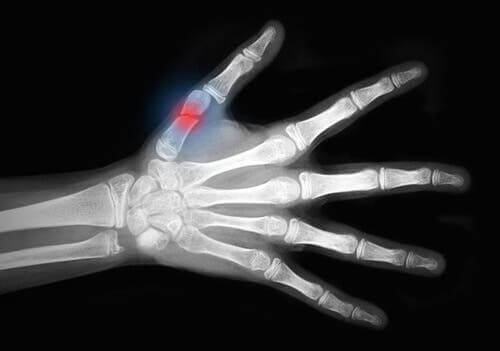

W medycynie urazy skalpacyjne to wszystkie te kontuzje i obrażenia, które powodują rozerwanie miękkich tkanek skóry na dużych obszarach i odsłonięcie kości. Problem ten dotyczy głównie kończyn.

Ostatnią kategorią są urazy skalpacyjne stopnia III. Obrażenia te są związane z poważnymi uszkodzeniami skóry i mięśni, takimi jak na przykład:

- Ciężkie urazy naczyniowe.

- Ostre zespoły ciasnoty przedziałów powięziowych. Jest to poważny stan, który wiąże się ze zwiększonym ciśnieniem w przedziale mięśniowym. Może prowadzić do uszkodzenia nerwów i mięśni, a także problemów z przepływem krwi.

- Urazy zmiażdżeniowe.

- Urazy goleniowe.

Jak widać, urazy skalpacyjne należą do najpoważniejszej grupy urazów tkanek miękkich.